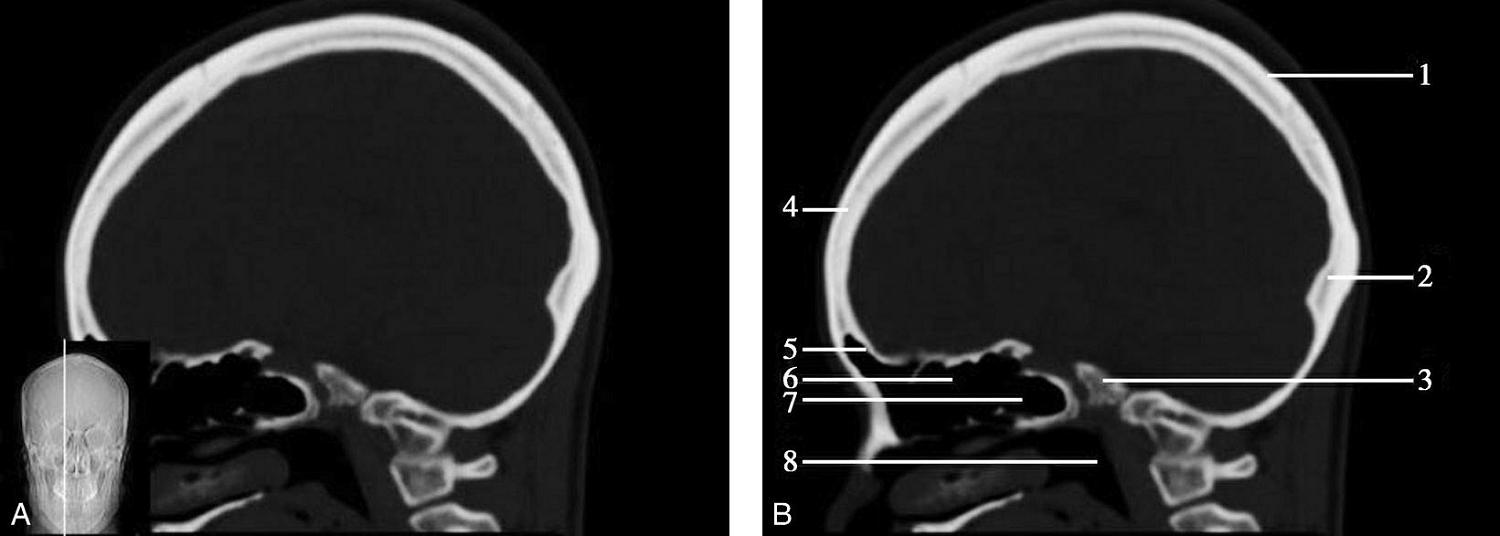

A.矢状面;B.矢状面标注

1.中央沟;2.扣带回;3.胼胝体体部;4.侧脑室;5.中脑;6.胼胝体膝部;7.穹隆;8.第三脑室;9.胼胝体压部;10.垂体;11.中脑导水管;12.第四脑室;13.脑桥;14.蝶窦;15.斜坡;16.小脑扁桃体;17.延髓

图1-2-60 正中矢状面骨窗CT

1.顶骨;2.枕骨;3.斜坡;4.额骨;5.蝶鞍

此层面可显示胼胝体全貌,它位于层面中央区域,是呈上凸下凹的弧形结构,由前向后分为嘴、膝、体和压四部分。扣带回环绕胼胝体上方,扣带沟位于扣带回的上方。大脑半球中部和后部分别可见较深且恒定的中央沟和顶枕沟。中央沟为是额叶顶叶分界标志。

胼胝体下方为侧脑室及穹窿,第三脑室借穹窿与前上方的侧脑室体部分开,背侧丘脑的内侧面以及中脑顶盖分别为第三脑室的外侧壁和底。第三脑室向前籍室间孔与侧脑室相通,向下经中脑导水管通第四脑室。中脑腔狭窄呈管状,即称为中脑导水管,中脑导水管畸形,常见者为导水管的分叉畸形和狭窄,其次可见中脑导水管膈膜,造成先天性脑积水。

脑干由中脑、脑桥和延髓组成,自第三脑室底向下后稍斜行,移行于颈髓。由上至下,脑干腹侧可见脚间池、桥前池和延髓池,脑干背侧可见大脑大静脉池、四叠体池和小脑延髓池。

垂体位于蝶鞍内,其前部为腺垂体,后上部分为神经垂体。垂体下方为鞍底及蝶窦,上缘因鞍膈存在而平直,垂体借垂体柄向上连于丘脑下部。垂体的前上方见视交叉和视束。斜坡作为前颅窝底的重要组成部分与多个重要结构相比邻,矢状位呈三角形,颅内肿瘤或颅外鼻咽部恶性肿瘤均可侵犯至此,原发肿瘤常见为脊索瘤。小脑幕居枕叶和小脑之间,向后下连接窦汇,向前至中脑后方游离,称小脑幕切迹。小脑幕下方为小脑扁桃体。成年人小脑扁桃体下缘由枕骨大孔向下疝入椎管超过5mm称为Chiari畸形,以矢状位显示最佳。